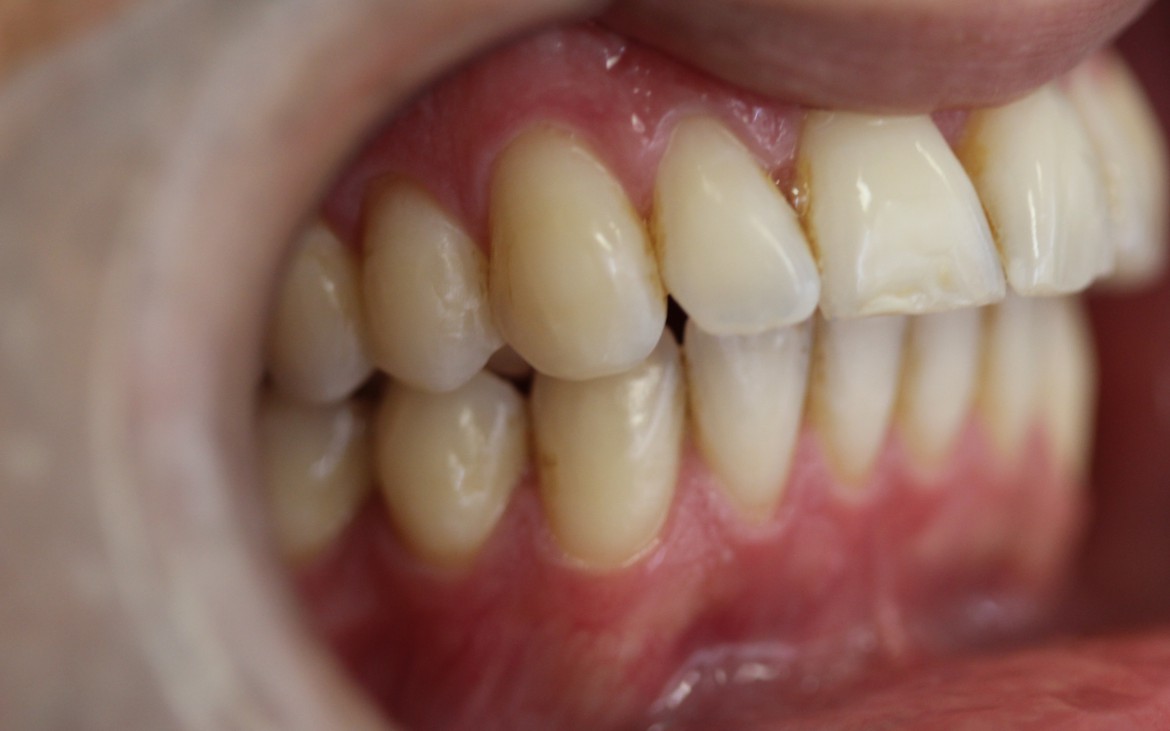

1 – Oclusão tipo classe II de angle com overjet acentuado de 6mm.

Maxila em posição centralizada em relação a base do crânio, mandibula retruida.

(vista lateral lado direito).